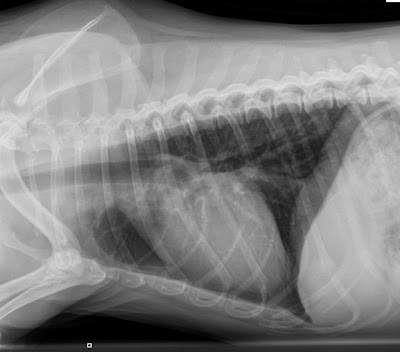

While the lungs are air-filled, the space surrounding the lungs, known as the pleural space, is normally devoid of air.

Pneumothorax refers to the accumulation of air with the pleural space.

In order to understand how a pneumothorax causes difficulty breathing, it helps to think of the chest cavity as an empty barrel into which the lung lobes expand as they inflate (like balloons filling with air). The lungs readily inflate with minimal effort because negative pressure (a vacuum effect) normally exists within the pleural space.

Fill the pleural space with air and the negative pressure is disrupted resulting in more effort required for lung expansion.

![]()  |

| Normal chest |